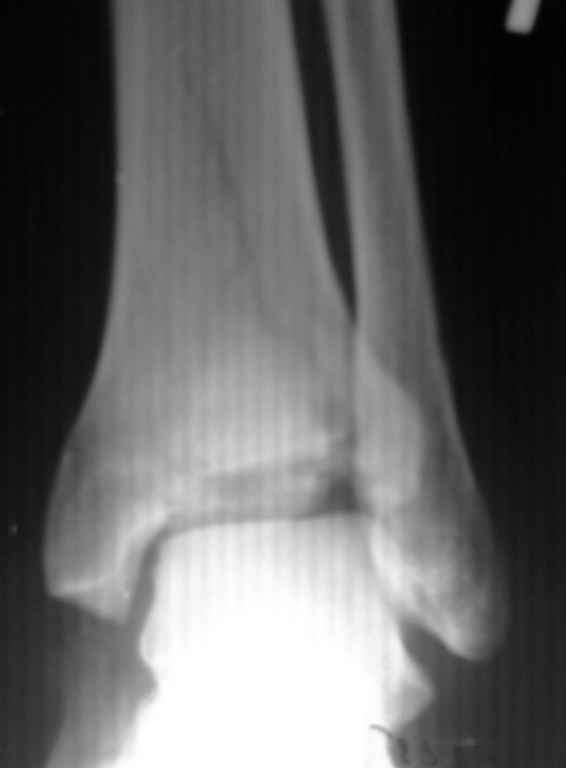

Приветствую ! Что то вторая проекция не прошла :((

Пересылаю

Здравствуйте. Я думаю что нужно использовать передний доступ. Заодно нужно мыть область гребень подвздошной оксти. Вполне может потребоваться аутопластика - все таки вполне серьезная импрессия.

Фиксатор - LCP Pilon Plate 2.7/3.5

Он позволит фиксировать при необходимости и сам трансплантат, и получить мостовидную фиксацию в области импрессии. Неблокируемые пластины в случае восстановления суставной поверхности с импрессионым дефектом будут иметь ограниченную дистальную опору, что неблагоприятно скажется на фиксации.